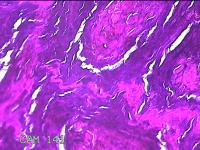

左侧足底结节

性别

男

年龄

49岁

临床诊断

鸡眼

一般病史

发现左侧足底结节伴隐痛不适1年余。

标本名称

大体所见

灰白粉红色带皮肤样结节1x0.7x0.2cm一个,表面糜烂,切开结节呈实性,切面灰白粉红色,质硬。